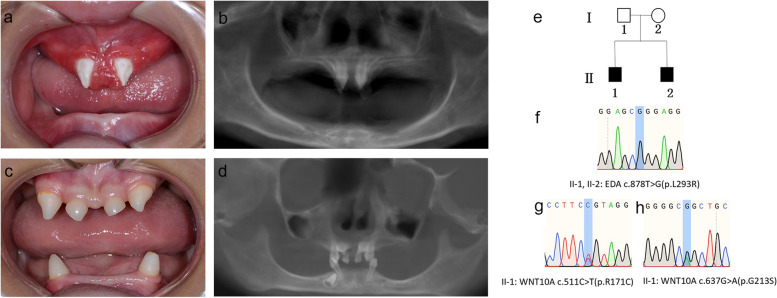

兩名分別為11歲和8歲的親兄弟因先天性牙齒缺失被轉(zhuǎn)診至同佳學(xué)基因具有合作關(guān)系的武漢大學(xué)口腔中心就診。經(jīng)患兒母親及兩名患兒本人簽署知情同意書后,醫(yī)護(hù)人員收集了兩位患兒的病史資料,拍攝了相關(guān)臨床照片,并采集了外周靜脈血樣本外送到佳學(xué)基因檢測進(jìn)行致病基因鑒定基因解碼分析。這對兄弟被診斷為低汗性外胚層發(fā)育不良(HED),均表現(xiàn)出典型的臨床特征,包括少牙(hypodontia)、毛發(fā)稀疏(hypotrichosis)、少汗(hypohidrosis)以及面部發(fā)育異常(facial dysmorphism)。有趣的是,哥哥的牙齒發(fā)育不全明顯比弟弟更為嚴(yán)重。哥哥下頜完全無牙,僅保留上頜兩顆中切牙;而弟弟則仍有部分前牙萌出。

體格檢查顯示,這對兄弟均表現(xiàn)出頭發(fā)稀疏、牙齒缺失及汗腺發(fā)育不良(圖1a-d)。兩人均具有X連鎖低汗性外胚層發(fā)育不良(HED)的典型面容特征:鞍鼻、嘴唇厚大、下頜尖翹以及眼周黑眼圈。

口腔檢查及錐形束CT(CBCT)掃描結(jié)果提示,哥哥(II-1)的所有乳牙及大多數(shù)恒牙均先天缺失,僅保留兩顆錐形上中切牙(#11、21)(圖1a-b)。由于下頜牙列完全缺失,他無法正常咀嚼或建立咬合關(guān)系。

弟弟(II-2)尚保留6顆乳牙(#51、53、61、63、73、83)及3顆恒牙胚(#11、21、43)(圖1c-d)。

Fig. 1

圖1:HED兄弟患者的牙齒特征與面部表現(xiàn)

a-b:**兄長(II-1)**的口腔狀況及全景X線片。

c-d:弟弟(II-2)的口腔狀況及全景X線片。

e:家系圖,黑色方塊代表HED患者。

f:DNA測序圖譜顯示兩位兄弟(II-1,II-2)攜帶

EDA基因雜合變異c.878T>G(p.L293R)

g-h:兄長(II-1)同時(shí)攜帶兩個(gè)WNT10A基因雜合變異:c.511C>T(p.R171C)和 c.637G>A(p.G213S)。

在兩兄弟中均檢測到EDA基因c.878T>G(p.L293R)的錯(cuò)義變異,但復(fù)合雜合型WNT10A基因變異(c.511C>T(p.R171C)和c.637G>A(p.G213S))僅在兄長中發(fā)現(xiàn)。

全外顯子組測序(WES)篩查顯示兄長存在3個(gè)錯(cuò)義變異:EDA基因第7外顯子的c.878T>G(p.L293R),以及WNT10A基因第3外顯子的c.511C>T(p.R171C)和c.637G>A(p.G213S)。生物信息學(xué)工具預(yù)測這三個(gè)變異均具有致病性(表2)。這些變異位點(diǎn)已提交至ClinVar數(shù)據(jù)庫(https://www.ncbi.nlm.nih.gov/clinvar/submitters/509028/)。其中WNT10A基因的c.511C>T和c.637G>A復(fù)合雜合變異被確認(rèn)為TA(缺牙癥)的致病突變。弟弟僅攜帶EDA基因的c.878T>G(p.L293R)錯(cuò)義變異。

母親臨床表型正常,未出現(xiàn)毛發(fā)、汗腺或牙齒相關(guān)異常。WES檢測顯示其為EDA基因c.878T>G雜合變異及WNT10A基因c.511C>T雜合變異的攜帶者。上述結(jié)果均經(jīng)Sanger測序驗(yàn)證(圖1e-h)。